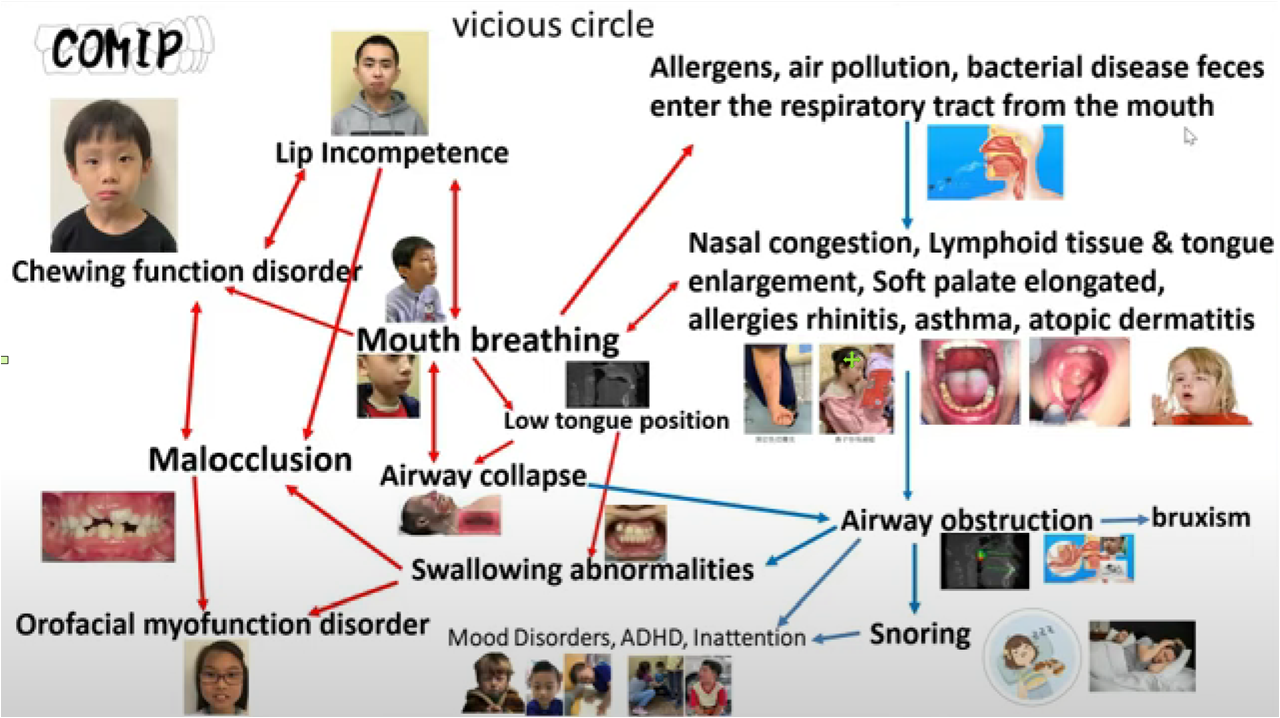

The COMiP two-stage correction system is a complete early correction system. In addition to aligning teeth and occlusal alignment, it can also correct muscle dysfunction, respiratory obstruction, help align teeth, and assist normal bone growth.

3. Why are respiratory obstruction, allergies and occlusal abnormalities comorbid

4. Why do muscle dysfunction occur and how to complete the four corrections

According to statistics, OSA is very prevalent, affecting about 34% of men and 17% of women aged 30-70 years. Due to the inconvenience of the use of positive pressure respirators, the effectiveness and convenience of oral devices can popularize the treatment of OSA. As a result, the C4 airway correction system has a large market to be developed. According to the "Overview of China's Oral Medical Service Market", in 2019, there were 885 dental specialties and about 7,000 dental departments in China(Including 6,287 secondary and tertiary general hospitals, 74 tertiary integrated traditional Chinese and Western medicine hospitals, 450 beauty hospitals, and 141 children's hospitals); National Medical Institution Inquiry System of the National Health Commission, As of December 24, 2020, there are 71,397 oral (dental) clinics nationwide. These hospitals or clinics will be the base for the promotion of the C4 airway correction system.

The market positioning of respiratory orthodontic systems is mainly aimed at those patients with snoring and obstructive sleep apnea (OSA), This is especially true in people who have difficulty or are unable to use positive pressure respirators. The advent of such devices offers an alternative that is more suitable for them, aimed at improving their breathing problems and sleep quality.

In addition, the system's custom design, including C4 braces, palate slow bone expansion and Angel therapy, allows it to more precisely meet the needs of patients and provide more effective and comfortable treatment options, which is also a major advantage in the market.

According to some reports, snoring and sleep apnea syndrome (OSA) are common problems for a large portion of the population, and these problems are likely to worsen as obesity rates increase. Snoring and sleep apnea are not just sleep problems, they are also linked to health problems such as heart disease, stroke, diabetes, and more. However, most of those affected are not diagnosed or treated.

COMiP two-stage early correction system. Our design has patents in many countries around the world. It is also the only system in the world that has four corrections. It is used in early correction. During the correction process, bone, teeth, muscle function and respiratory tract correction are gradually completed, providing a comprehensive solution. Problems with growing children. How to complete correction in two stages

There are many causes of malocclusion in early childhood. Heredity is usually the main cause. Other causes include trauma to the teeth, premature loss of deciduous teeth, and some bad oral habits (such as finger sucking, nail biting, lip biting, and tongue sticking out). Some mixed teeth Malocclusion in the orthodontic period can be treated early. The benefits of early treatment are to get rid of bad oral habits early, improve the appearance of the child, guide the permanent teeth to grow in the correct position, avoid the need for tooth extraction for correction in the future, or reduce the difficulty of correction in the future.

Orthodontic intervention must be dealt with in a timely manner. However, many parents do not know that bad habits such as mouth breathing and improper tongue positioning are also the main causes of children's irregular teeth. For example, "open bite" is mainly caused by children's bad habits. evolved.

In addition to the common traditional correction and Invisalign for children, MRC muscle function correction is also an option for early correction treatment. Timely training of oral muscles and the development of the habit of tongue pressing against the roof of the mouth can greatly reduce the error rate of future tooth and palate growth. Grasping the advantages of children's golden period of orthodontics can guide the development of the mandible, provide space for the permanent teeth to sprout, increase the stability of the bite, enhance the self-confidence of growth, reduce the complexity of the second stage of correction, and reduce the probability of tooth extraction in the future.